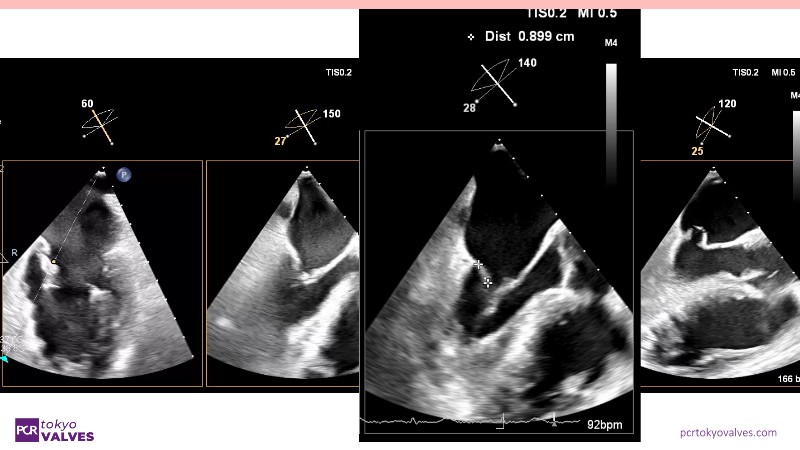

Explore the latest advancements in TEER therapy with this PCR Tokyo Valves 2025 session dedicated to MitraClip. Through expert-led case discussions, gain a deeper understanding of complex scenarios, including restricted posterior leaflet in functional mitral regurgitation, commissure lesion (A3P3), and MitraClip combined with Amulet.